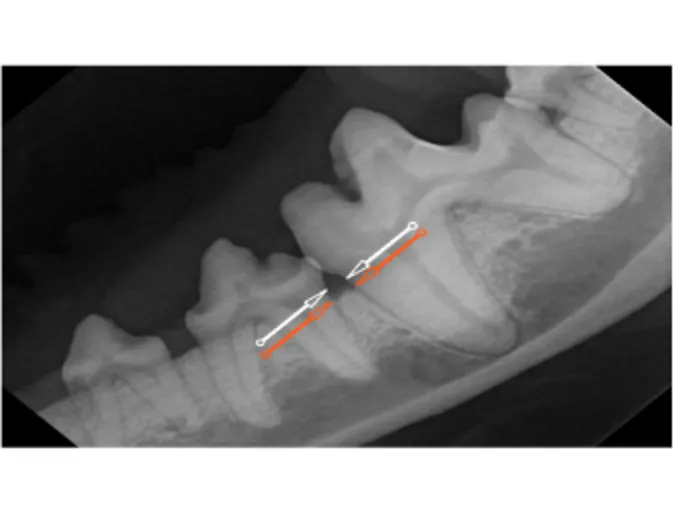

White arrows are where the bone should be and orange arrows indicate the level of bone loss.

Notice extensive tartar and extremely reddened/inflamed gum tissue.